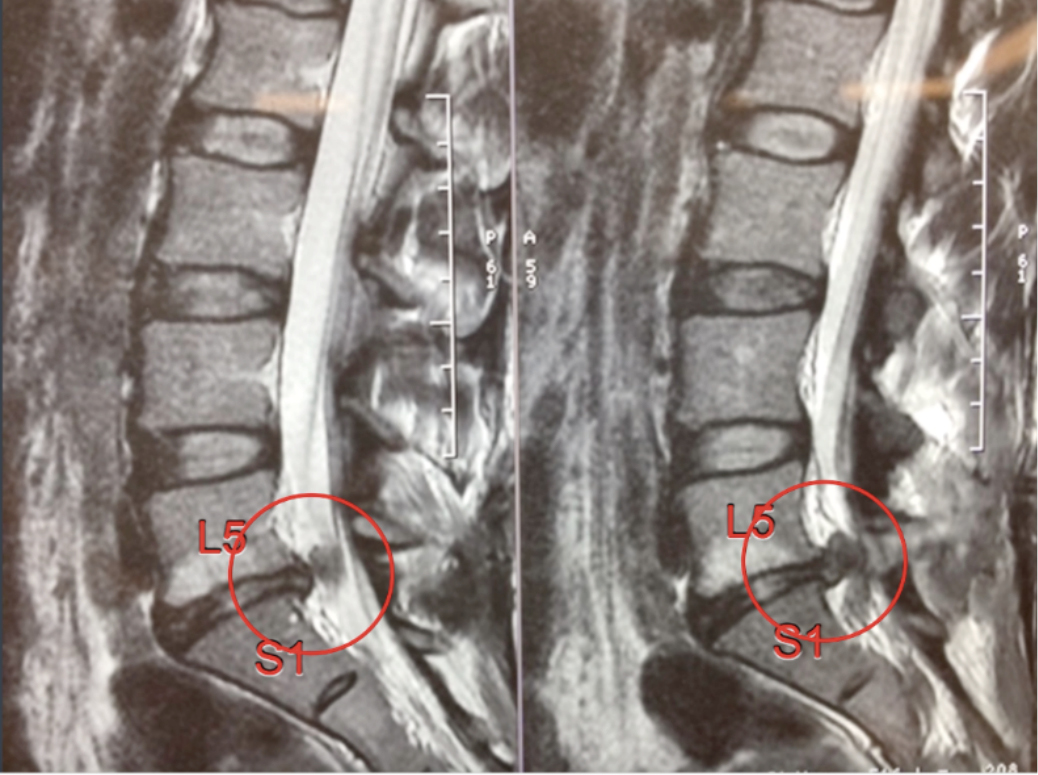

Рентген шейных позвонков при спина бифида

Раздел: Фотозарисовки